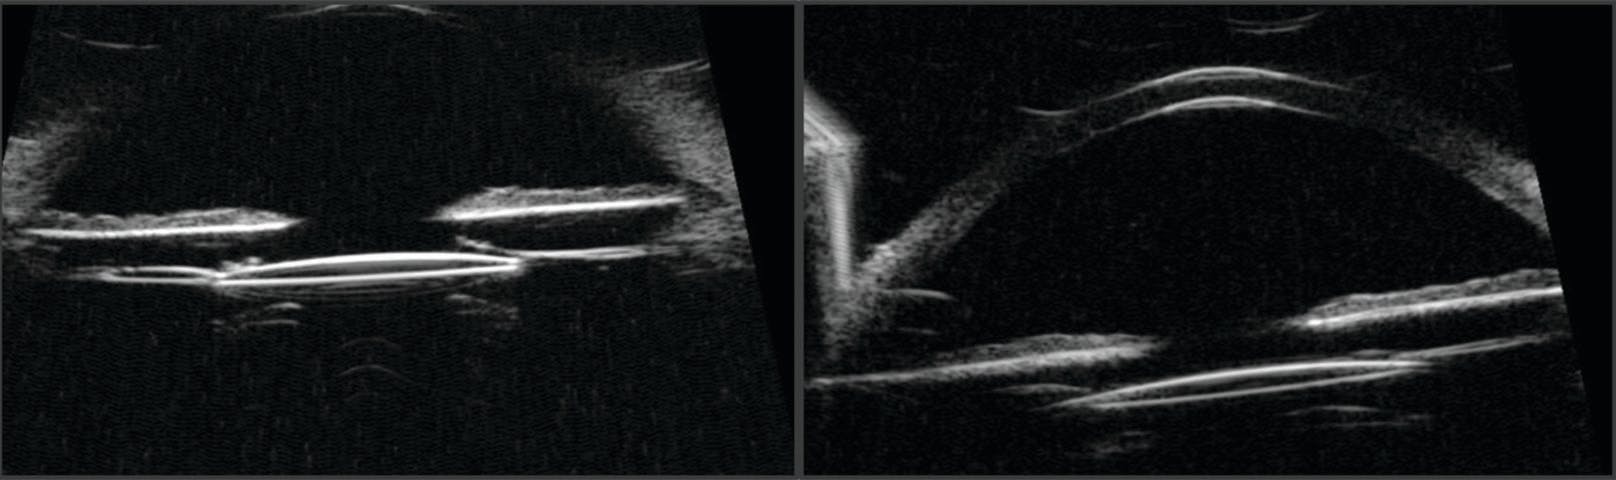

We have recently encountered cases of in-the-bag UGH syndrome resulting from subtle pseudophacodonesis in patients with dead bag syndrome (DBS). First described by Samuel Masket, MD, DBS is characterized by late IOL dislocation due to a capsular bag that lacks sufficient structural integrity to provide long-term support.3-5 In eyes with DBS, the diaphanous, floppy, and sometimes splitting capsule may result in zonulopathy and pseudophacodonesis. Peripheral dislocation of the IOL haptics through the equator of the capsule may also occur, particularly if the bag splits spontaneously. Preoperatively, ultrasound biomicroscopy (UBM) can be a critical step in assessing bag integrity, IOL position/tilt, and a calcific Soemmering ring as possible etiologies of UGH syndrome.

On examination, the IOL was in the capsular bag, which exhibited minimal to no fibrosis (Figure 1A). Retroillumination at the slit lamp revealed peripheral iris transillumination defects at the 2 and 8 clock positions (Figure 1B), raising clinical suspicion that the one-piece acrylic IOL was in the sulcus or UGH syndrome had developed. UBM confirmed that the IOL was in the bag without visible tilt or evidence of prominent iris chafing induced by capsular fibrosis or Soemmering ring material (Figure 2).